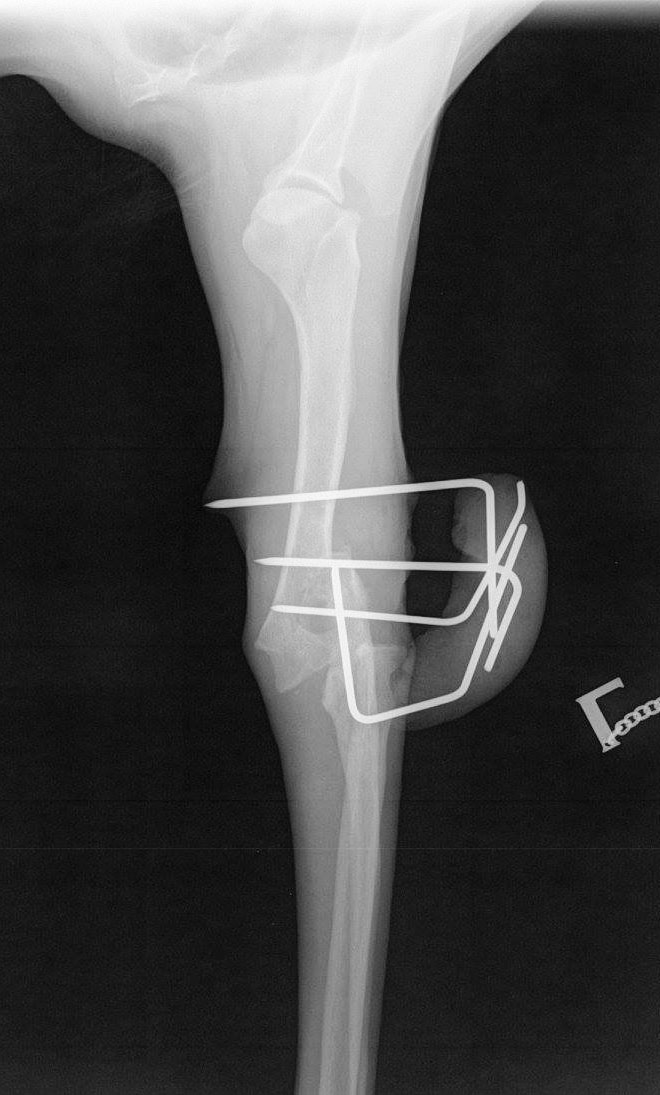

Mit großem Bammel brachten wir Picco zum festgesetzten Termin nach Hannover. Mir war total flau im Bauch und die Nacht davor habe ich kaum geschlafen. Zum Glück wusste Picco nicht, was ihn erwartet. Am frühen Nachmittag kam der erlösende Anruf, die OP ist gut verlaufen, Picco bereits wieder halbwegs wach. Leider war der ursprüngliche Plan, das Gelenk beweglich erhalten zu können, nicht durchführbar. Auf Grund des doch schlimmeren Zustandes des Innenlebens im Gelenk als erwartet entschlossen sich die operierenden Ärzte zur Versteifung. Es waren sogenannte Kirschnerdrähte zur Ostheosynthese eingesetzt worden, um das Gelenk zu fixieren. Diese müssen 6-8 Wochen im Knochen verbleiben. Das ganze nennt sich Fixateur Externe. Sieht schlimmer aus als es für den Patienten ist.

Als erstes wurden zwei Röntgenbilder angefertigt, um die Weiterentwicklung zu sehen. So ganz zufrieden waren sie noch nicht, aber drin bleiben sollten die Drähte nicht mehr, da keine weitere Verbesserung zu erwarten wäre. Die OP ging schnell, nur danach mussten wir doch recht lange warten, bis wir ihn abholen konnten. Die Entfernung hat problemlos funktioniert, Picco war halbwegs wach, als wir ihn wieder bekommen haben. Ob die OP mit der Fixierung des Gelenks ein Erfolg war, wird sich in den nächsten Wochen zeigen. Im worst Case muss das Gelenk vollständig versteift werden und eine Platte eingesetzt werden. Die in den Raum gestellte Amputation möchte ich vermeiden, da Picco so gut mit dem Beinchen zurecht kommt, dass es hoffentlich überflüssig sein wird. In der Zeit soll Picco Physio bekommen, nur finde ich hier leider keine gescheite für Tiere. Schwimmen werden wir einführen, sobald Picco ins Wasser darf (so in ca. 10 Tagen). Massage und das Training der Beweglichkeit hat mir unser TA gezeigt.